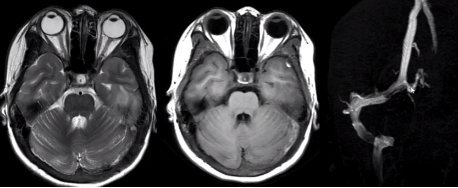

(1)蛛网膜下腔出血

颅内血管破裂,血液进入蛛网膜下腔。

病因:动脉瘤破裂(最常见)、高血压、血管畸形、外伤。

(上下滑动查看全部图片)

(2)前交通动脉瘤破裂出血